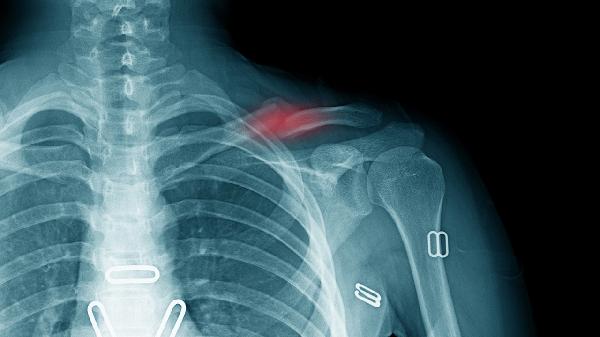

鎖骨骨折保守治療后一般需要4-6周開始逐步鍛煉,具體時(shí)間取決于骨折愈合情況、年齡、康復(fù)計(jì)劃、營(yíng)養(yǎng)狀態(tài)和并發(fā)癥等因素。

骨折線模糊是開始鍛煉的基礎(chǔ)指標(biāo),需通過X光確認(rèn)骨痂形成。臨床愈合通常需3-4周,此時(shí)可進(jìn)行被動(dòng)關(guān)節(jié)活動(dòng)。完全負(fù)重訓(xùn)練需等待骨性愈合,約需8-12周。

合并臂叢神經(jīng)損傷需延遲至6周后鍛煉。出現(xiàn)反射性交感神經(jīng)營(yíng)養(yǎng)不良時(shí),應(yīng)優(yōu)先進(jìn)行疼痛管理。二次移位風(fēng)險(xiǎn)高的粉碎性骨折需延長(zhǎng)固定時(shí)間2-3周。